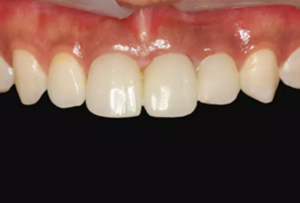

圖16 軟組織成形后口內(nèi)像

圖23 最終修復(fù)后即刻口內(nèi)像

圖25 最終修復(fù)后復(fù)查口內(nèi)像